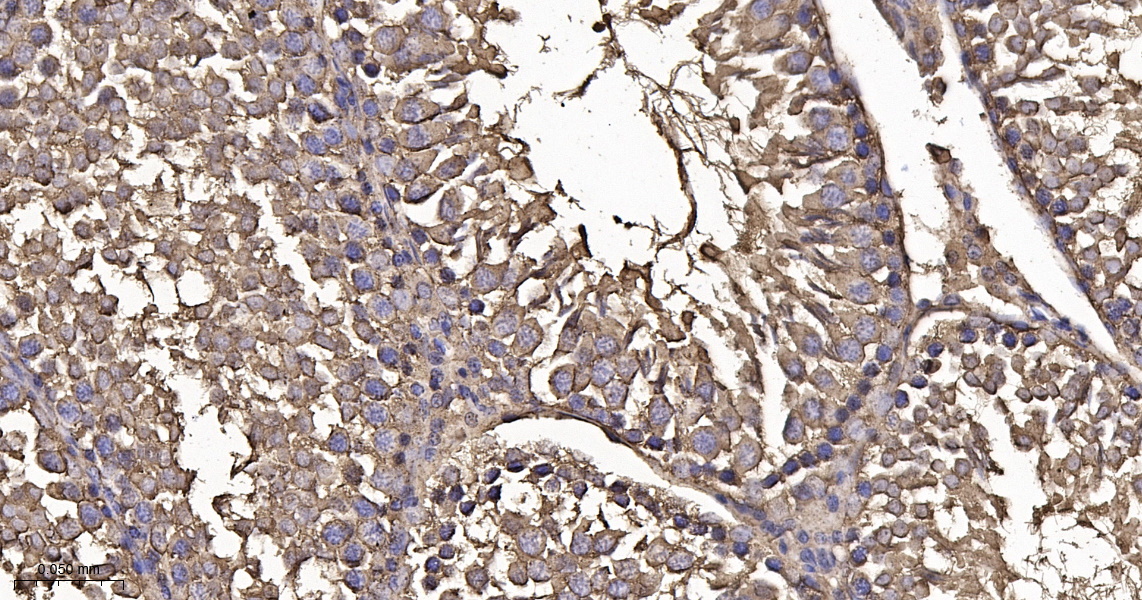

• IHC-P

IHC-P IHC-P1:100-500